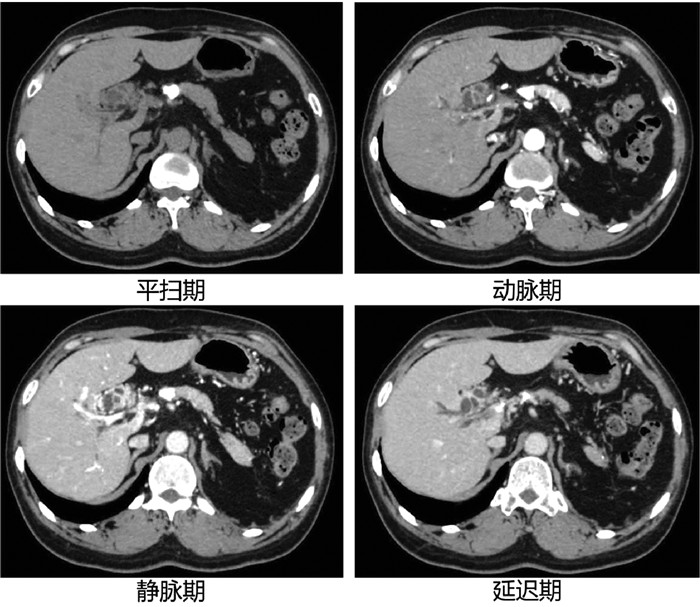

Intrapancreatic accessory spleen misdiagnosed as pancreatic neuroendocrine tumor: A case report

Xuxiang XIA, Guoyue LYU, Xiaotong QIU, Wei QIU

2022, 38(2): 436-438. DOI: 10.3969/j.issn.1001-5256.2022.02.036

Abstract(1098) HTML (844) PDF (2885KB)(44)

Abstract: